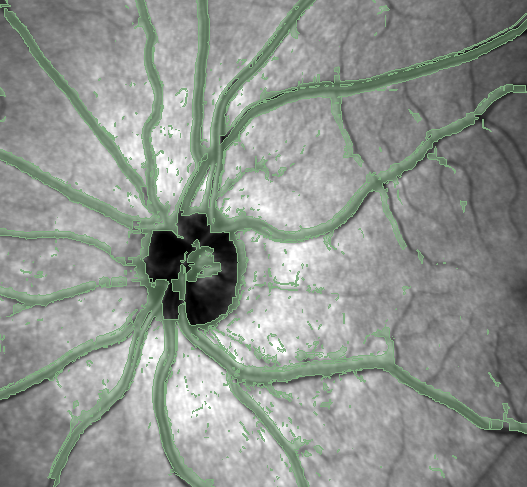

Vessel Segmenter creates a segmentation map over IR eye scans, allowing for easier segmentation as the consumer does not have to segment every edge pixel tediously. Normally, we have to identify the vessel type, either arteries or veins, and then meticulously try and shade in every pixel for each vessel. When using our project, you just need to put the Infrared Eye PNG into the program, and it will give you a segmentation mask that can be converted to STL, and you can overlay it with the PNG file in Slicer. From there, you just need to identify the type of vessel, draw a rough outline, and then intersect the masks to create a much more accurate and speedy segmentation.

We spent over 6 hours of hard work making this work. We worked collaboratively on a Google Collab Notebook. We used convolutional neural networks from opencv to detect edges on the IR scans and created pixel masks to indicate edges. Image blurring and normalization techniques were used to improve its accuracy further. Then, we iterated through pixels using the positions of edges, the color of the pixel, and other data to determine for each pixel if it’s part of a vein.

We were able to use a convolutional neural network to accurately identify the exact locations of edges across an IR image. Then, we devised a method of filling in non-edge pixels to generate an accurate segmentation mask for the IR scan. We are confident that this segmentation mask will significantly improve the efficiency of annotating such images